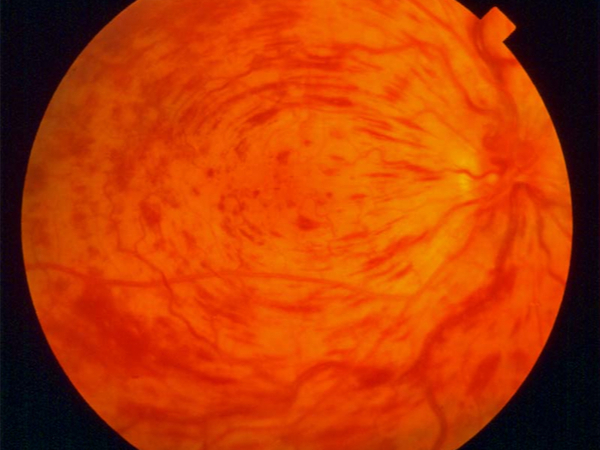

Esame del fondo oculare

Un esame del fondo retinico è sufficiente per porre diagnosi di occlusione venosa retinica.

Fluorangiografia retinica

La fluorangiografia è un esame fondamentale per lo studio della retina. Si esegue iniettando in vena un colorante fluorescente e scattando poi delle foto con uno strumento specifico.

Nella forma ischemica è essenziale per monitorare l'estensione dell'ischemia e impostare un eventuale trattamento laser.